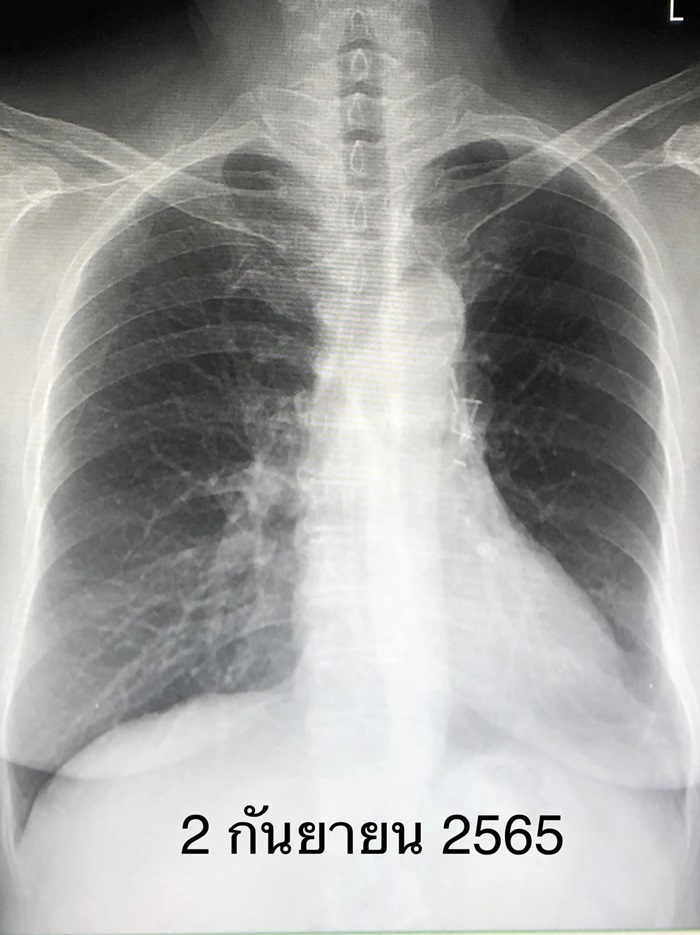

สรุปผู้ป่วยรายนี้ไม่มีอาการ ไม่เคยสูบบุหรี่ แต่หายใจควันธูปต่อเนื่อง เป็นมะเร็งปอดระยะ 2A (มะเร็งปอดระยะ 2A คือมะเร็งขนาด 4-5 เซนติเมตร และไม่แพร่กระจายเข้าต่อมน้ำเหลือง หลังผ่าตัดมีโอกาสรอดชีวิตที่ 5 ปี ร้อยละ 60) ติดตามผู้ป่วย 7 ปี หลังผ่าตัด ไม่พบมะเร็งปอดกลับมาใหม่ ถือว่าหายขาดจากโรคนี้ (ดูรูป) ผู้ป่วยได้เลิกจุดธูปหลังผ่าตัดปอด